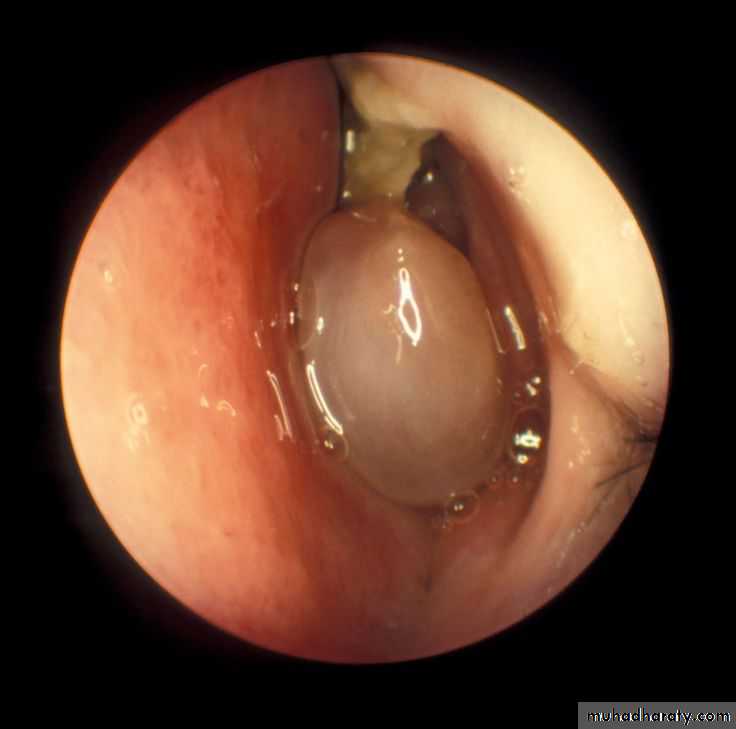

Nasal polyp

Polypoid projection from nasal mucosa , gelatinous in consistency with smooth surface. Usually bilateral (cf with neoplasm)It consist of edematous nasal mucosa contain, blood vessels, mucus glands & infiltrated by chronic inflammatory cells & eosinophils.

It result from allergic & inflammatory reaction